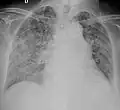

A case of miliary tuberculosis in an 82-year-old woman:

-

X-ray, 13 days after onset, showing bilateral interstitial infiltrates -

X-ray, 22 days after onset, showing extensive bilateral reticulo-nodular infiltrates -